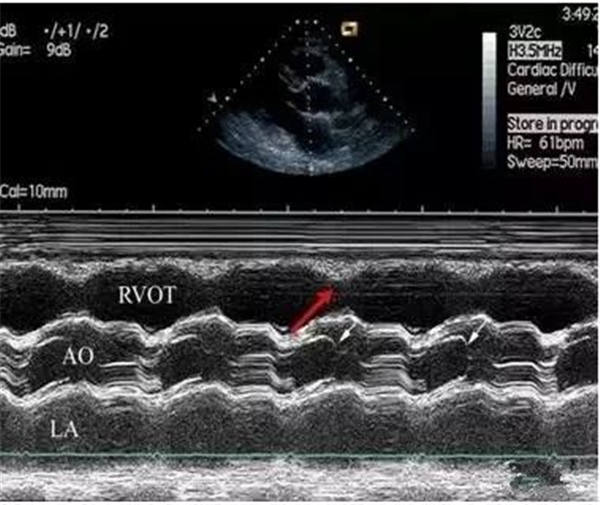

上圖:

右室壁運動幅度減低

正常情況下,右室前壁運動幅度應>5 mm,右室游離壁運動幅度會>8 mm,但對肺栓塞(PTE)患者,右室壁基底部至游離部運動幅度減低,甚至消失。